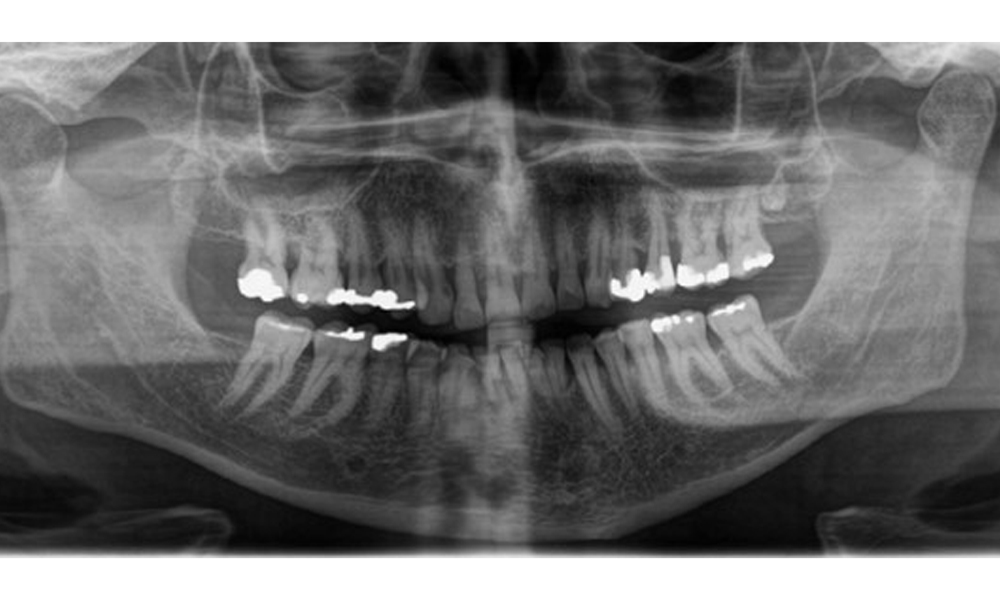

Radiologischer Befund

Es zeigt sich ein vollbezahntes Erwachsenengebiss mit einem generalisiertem Knochenabbau zwischen 20-50% und multiplen vertikalen Knocheneinbrüchen. Radiologisch ist keine kariöse Läsion sichtbar. (Abb. 7)

Panoramaschichtaufnahme zur Darstellung des generalisierten radiologischen Knochenabbaus mit multiplen vertikalen Defekten zwischen 20-50%. © Dr. R. Krapf

Abb. 7 Panoramaschichtaufnahme zur Darstellung des generalisierten radiologischen Knochenabbaus mit multiplen vertikalen Defekten zwischen 20-50%. © Dr. R. Krapf